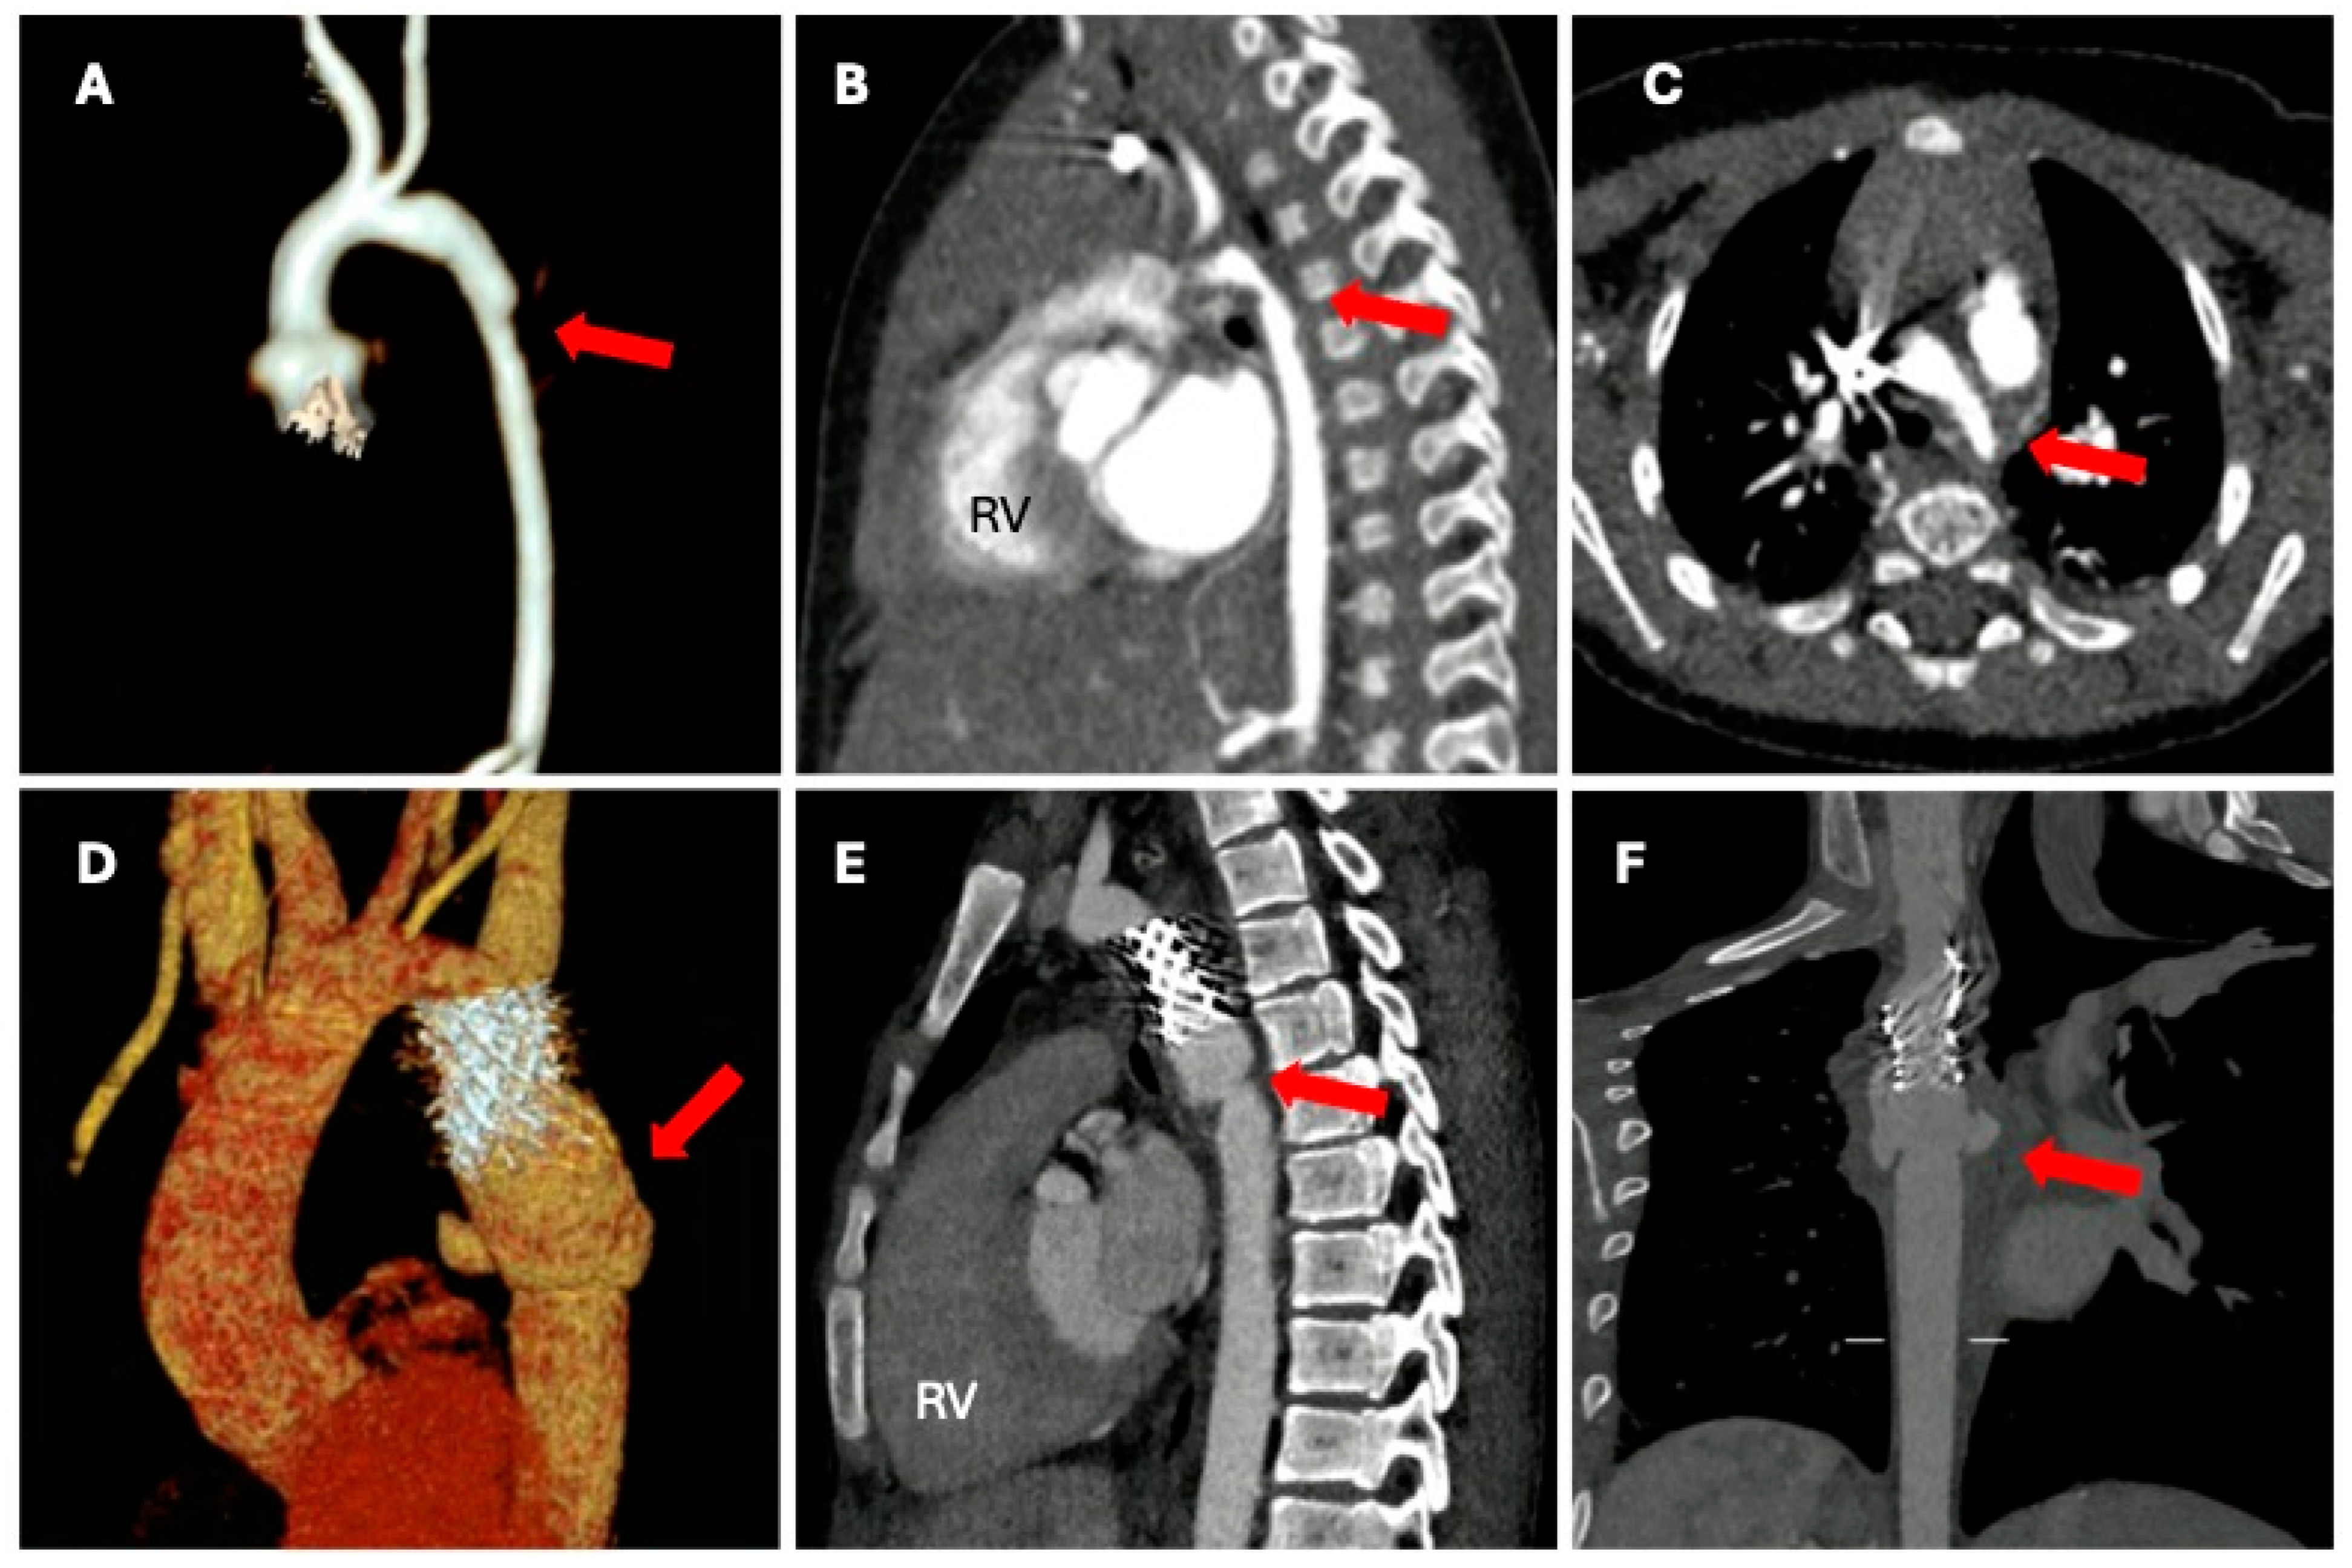

4. Computed Tomography